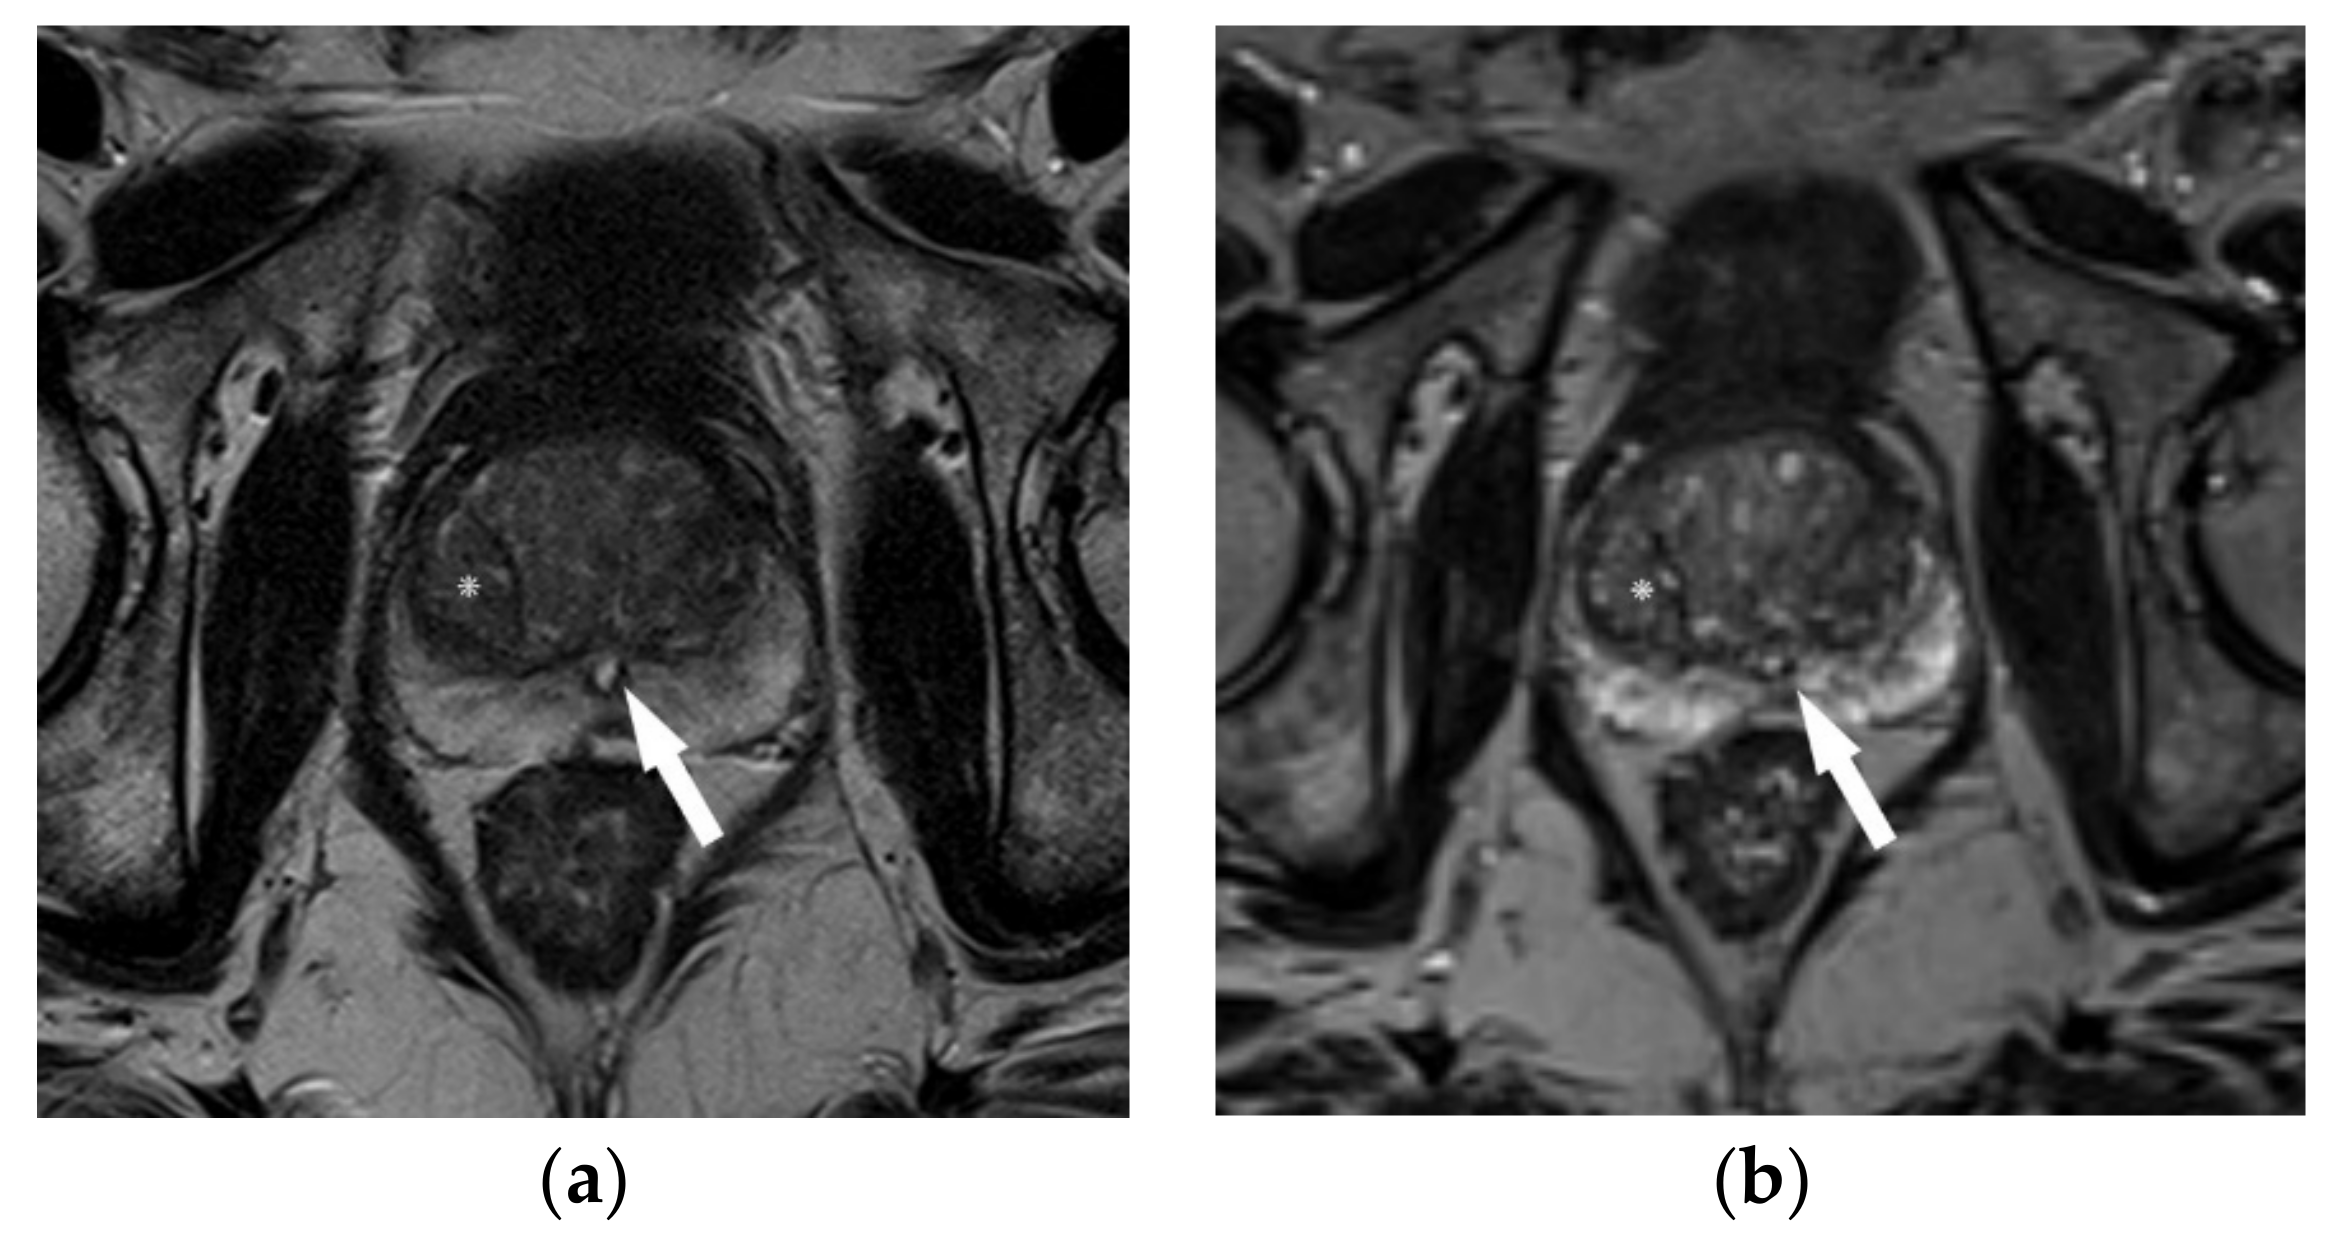

3.2. Shortening T2-Weighted Acquisition Times